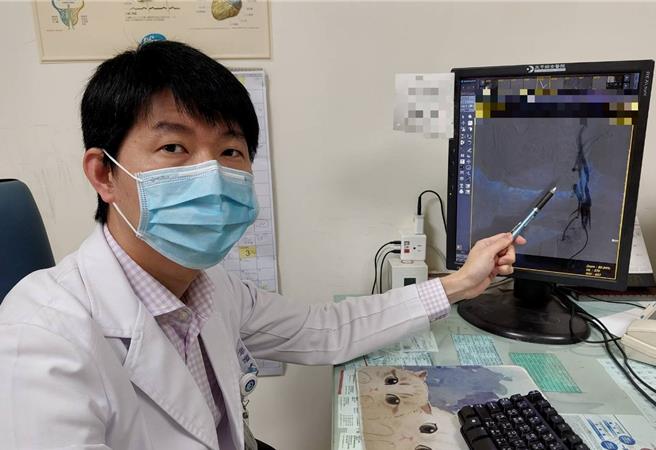

大千綜合醫院心臟血管內科醫師羅健賢表示,頸動脈狹窄基本的治療方法為藥物治療,但當狹窄嚴重時,則須考慮頸動脈內膜切除手術或現行的微創治療-頸動脈支架置放術。頸動脈支架置放術只需局部麻醉,由鼠蹊部的股動脈穿入,經由導管到達頸動脈狹窄處後,以氣球擴張並將支架固定於狹窄處。其喉返神經受損率及治療困難度比傳統的頸動脈內膜切除手術較低,且同樣能達到預防腦中風的效果,目前的頸動脈支架置放術再加上遠端保護裝置,更可以減少併發症,施行成功率超過95%以上。